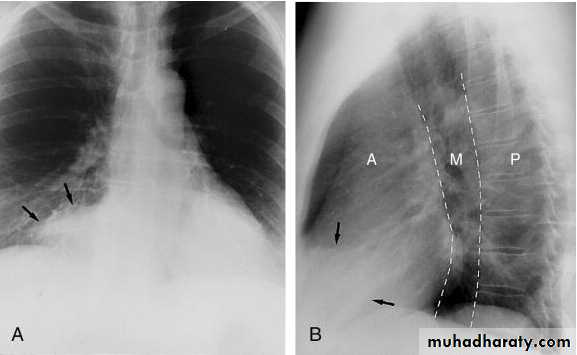

Pericardial fat pad. A, A soft tissue mass (arrows) is seen in the right cardiophrenic angle on the frontal chest x-ray. B, It also is seen in the anterior mediastinum on the lateral view. On this view, the anterior (A), middle (M), and posterior (P) portions of the mediastinum have been identified.